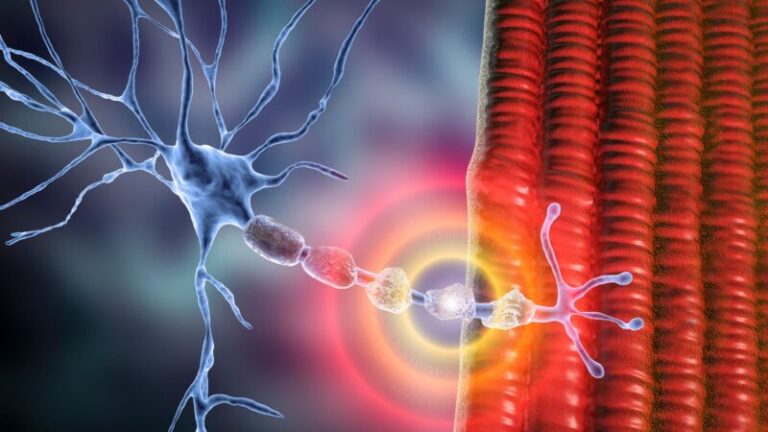

Hoại tử vô mạch chỏm xương đùi là một loại hoại tử xương do gián đoạn cung cấp máu cho đầu trên xương đùi. Thiếu máu cục bộ chỏm xương đùi gây chết tủy và tế bào xương, dẫn đến hoại tử đoạn chỏm xương đùi.

Do tuần hoàn bàng hệ bị hạn chế, nếu cấp máu cho chỏm xương đùi bị gián đoạn có thể dẫn đến thiếu máu cục bộ. Nếu nguồn cung cấp máu không phục hồi kịp thời, điều này sẽ dẫn đến cái chết dần dần của các tế bào xương, hoại tử, sau đó là xẹp bề mặt khớp và cuối cùng là thoái hóa khớp.

Các cơ chế sinh lý bệnh gây hoại tử vô mạch chỏm xương đùi đôi khi không rõ ràng và thường được cho là do nhiều yếu tố. Dù yếu tố thúc đẩy là gì, kết quả về cơ bản là các tế bào xương và tủy xương bị chết đi do lưu lượng máu đến xương dưới sụn của chỏm xương đùi bị giảm hoặc mất. Sự chết tế bào này cuối cùng sẽ dẫn đến xẹp chỏm xương đùi và kéo theo đó là thoái hóa khớp nếu không được điều trị hiệu quả ngay từ giai đoạn đầu.